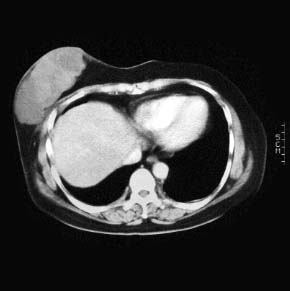

CaseKH02

- Age/Sex: 48F

- Chief Complaint: 乳房腫瘤

- Clinical Course:

- Lab. Data:

- Images:

- CT(1)

CT(2)

CT(2)

- CT(3)

CT(4)

CT(4)

- DSA1

- DSA2